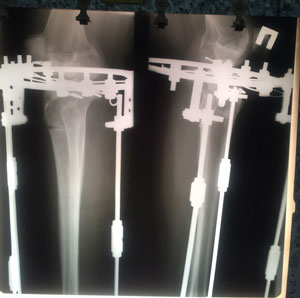

Диагноз: вальгусная деформация голеней (Х - образная)

Дата операции - 16.07.2019г.